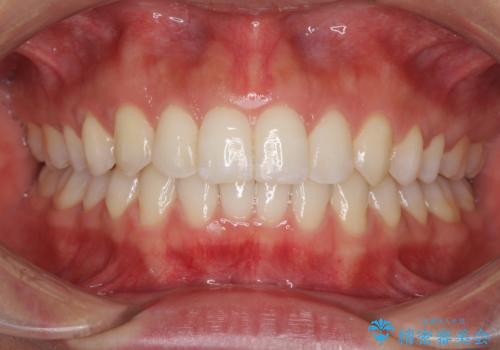

ワイヤーによる全体的ながたつきの矯正治療